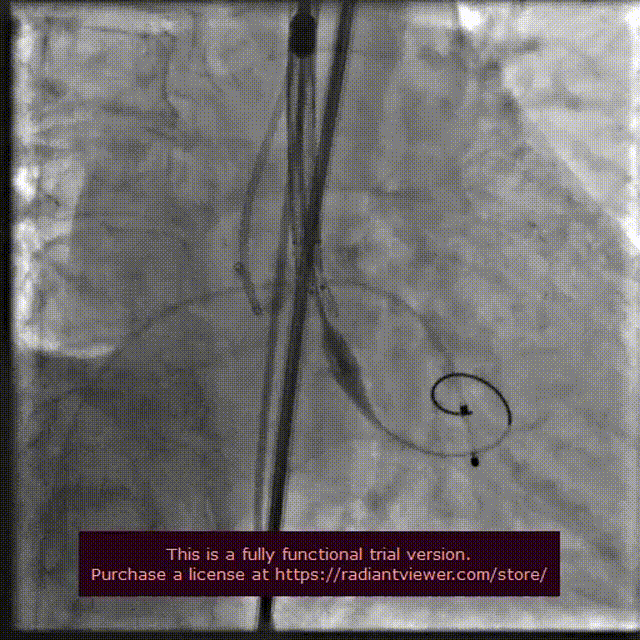

22 mm球囊预扩张

输送系统定位